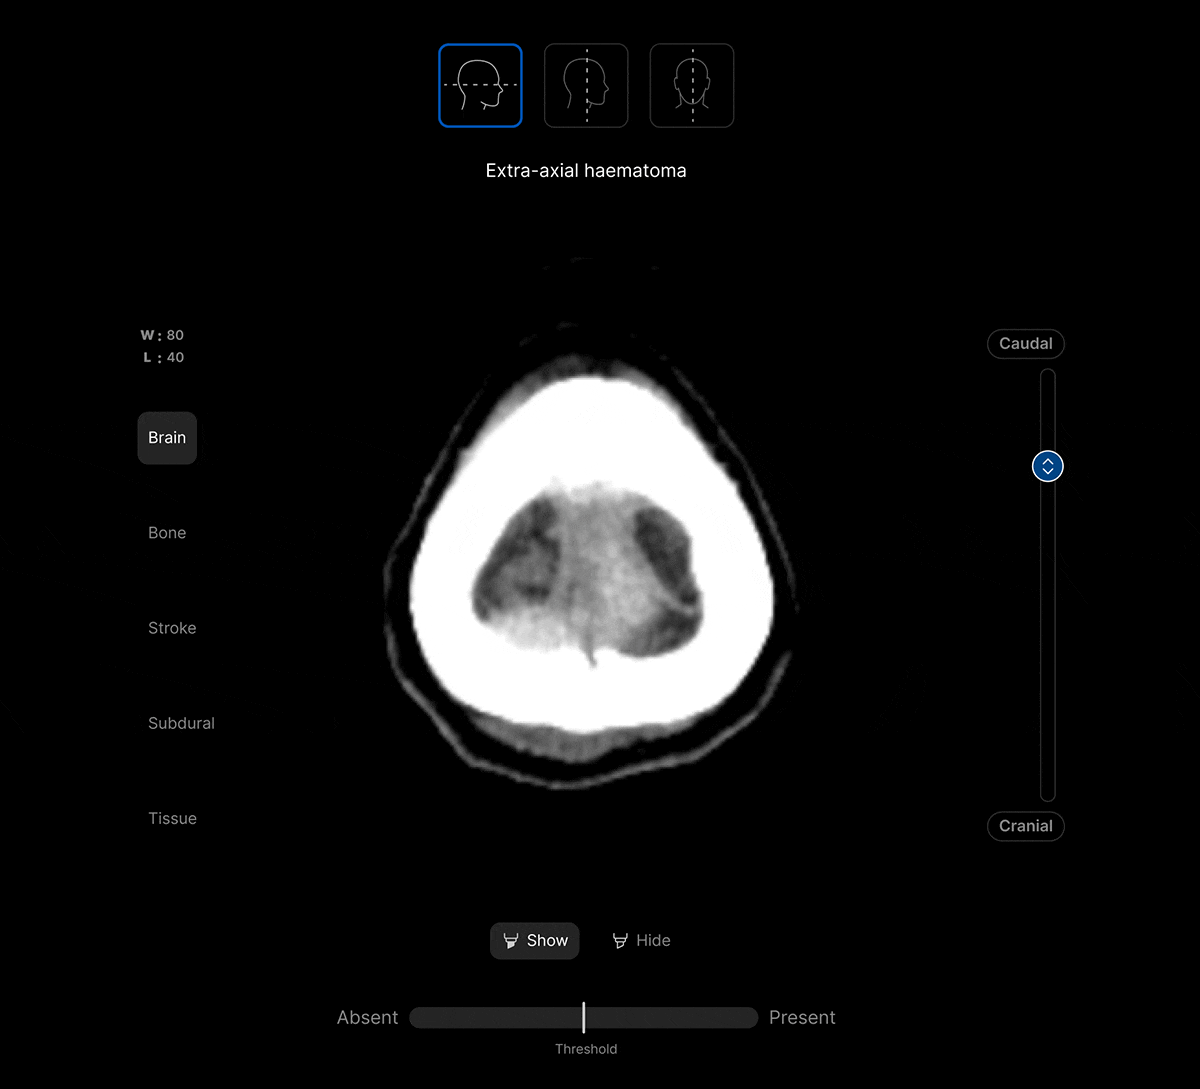

Harrison.ai CT Brain (CTB) is our comprehensive imaging AI solution for non-contrast head CT studies that detects up to 130 findings in under 90 seconds, boosting emergent and incidental capture while surfacing urgent cases for review first – all within the workflow you’re used to.

The UI integrates seamlessly with PACS/ RIS, displaying a resizable, no-click overlay window with findings and localisation.

Customisable features.

Customisable thresholds, for individual findings (to optimise for sensitivity / specificity) to tailor the workflow to your clinical setting or population.

Maximise clinical value and simplify your workflow with a single comprehensive solution for non-contrast head CT studies, identifying up to 130 findings. No need to juggle multiple solutions for different findings.